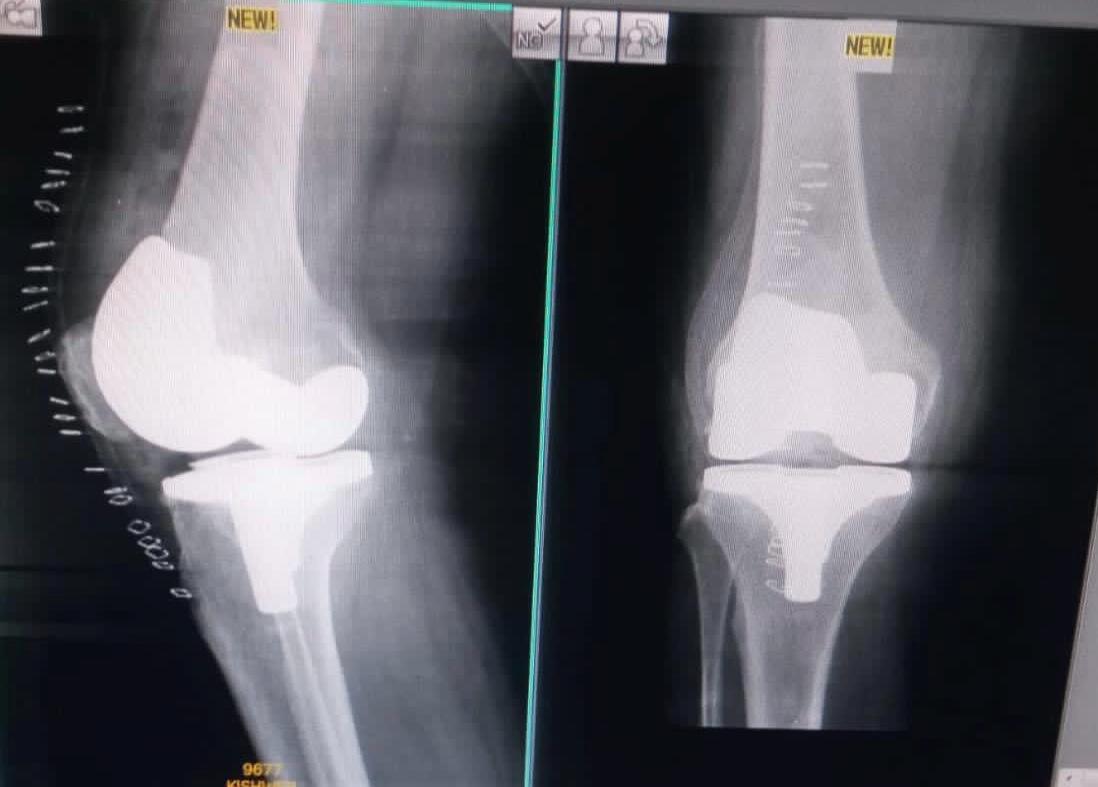

Joint replacement surgery is offered for patients suffering from severe joint pain, stiffness, and reduced mobility due to degenerative joint conditions. The goal of joint replacement is to relieve pain, restore movement, and improve overall quality of life through modern surgical techniques and structured post-operative care.

Total knee and total hip replacement surgeries are performed for advanced joint damage where conservative treatment is no longer effective. These procedures help restore joint function, reduce chronic pain, and allow patients to return to daily activities with improved mobility and comfort.